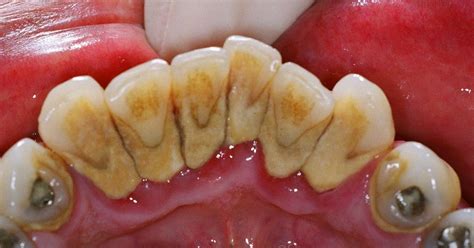

El sarro dental, también llamado cálculo dental, es una placa bacteriana que se ha endurecido debido a los minerales presentes en la saliva. Todo comienza con la placa dental, una película transparente y pegajosa que se forma constantemente en nuestros dientes.

Si no se elimina correctamente (con un buen cepillado y el uso de hilo dental), esta placa se mineraliza y se convierte en sarro, especialmente en zonas como detrás de los dientes inferiores.

El sarro, o cálculo dental, es placa bacteriana que se ha endurecido por los minerales de la saliva.